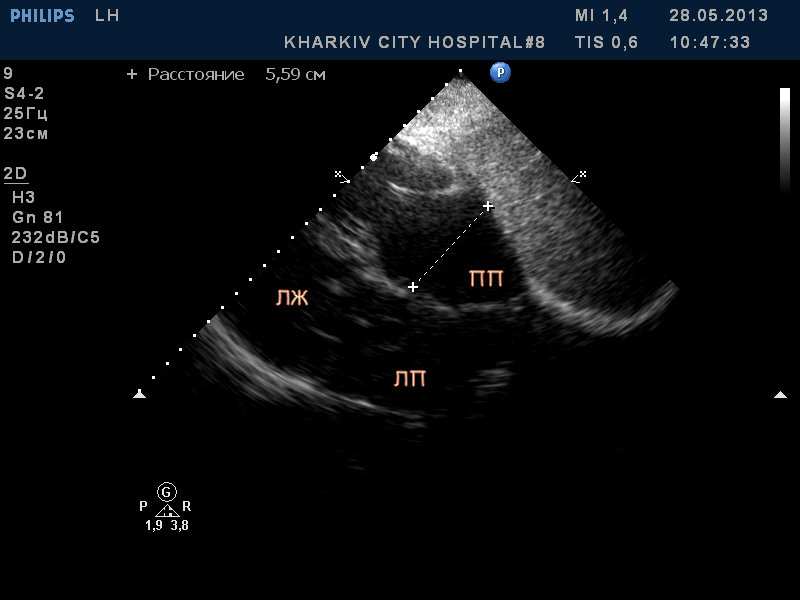

Пациентка 83 лет. Жалобы на сильную одышку в теч. последнего месяца.

В полости левого желудочка в базальном сегменте имеется образование с неровным контуром до 2.4см- вероятно миксома левого желудочка.

кальциноз створок АК, дилатация левого предсердия, правых полостей, выраженная недостаточность ТК и клапана ЛА, гипертрофия левого желудочка. Дополнительные косые хорды левого желудочка. Высокая ЛГ (АТ/ЕТ- 0.20 Рсред. ЛА-69мм рт.ст.).